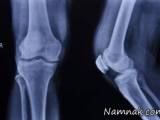

تغذیه بعد شکستگی استخوان و مواد مغذی برای جوش خوردن استخوان

استخوان ها اسکلت بدن را تشکیل می دهند و از اندام ها محافظت کرده و عضلات را ثابت نگه می دارند تغییراتی در رژیم غذایی می تواند به التیام استخوان ها پس از شکستگی و بهبود و تقویت سلامت استخوان ها کمک کند.

ترمیم استخوان شکسته چگونه صورت میگیرد؟